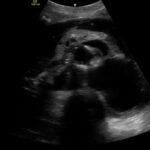

Although uncommon, acute aortic dissections are a life-threatening, cannot miss diagnosis for the emergency medicine clinician. Point of care ultrasound can play an integral role in the initial work up of the undifferentiated patient. While not initially utilized to make the diagnosis of aortic dissection, the ultrasound images obtained in this case describe key findings on ultrasound vital for an emergency clinician to recognize. It is essential for emergency medicine clinicians to differentiate an aortic dissection from other causes of chest pain and abdominal pain because the quick mobilization of resources plays a key role in the management and outcome of such patients.